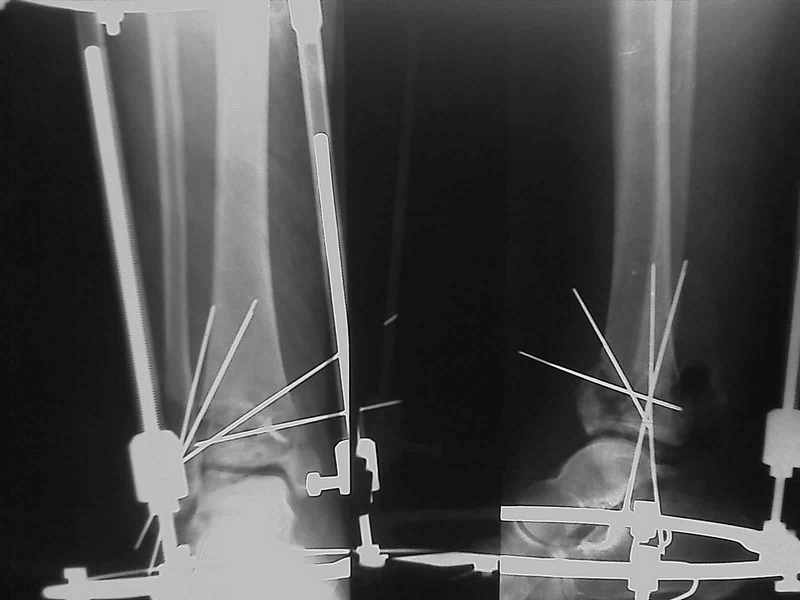

Добавлены КТ снимки. Прошу прощения за качество.

С уважением, Коваленко А.Н.

Снова приветствую вас, коллеги. К моменту вступления в обсуждение аксакалов, операция была, увы, выполнена(31.10.07.) Начали с доступа к наружной лодыжке, произвели ее фиксацию спицами, развернули кусок заднего края, наложили дистрактор, затем произвели дистракцию, фиксацию спицами дистального эпиметафиза б/бк,Рентгено-контроль. синтез наружной лодыжки 1/3пластиной. из двух коротких разрезов сформирован канал под медиальную тибиальную пластину LCP. Края ран ушиты без натяжения. Прочувствовать жесткость фиксации винтами с угловой стабильностью не удалось, поэтому дистрактор оставлен на энное время.

На представленных R-снимках не окончательный вид после остеосинтеза. Дистальная опора давила на стопу, пришлось ее сместить проксимально, в рез-те чего, она закрыла щель сустава, последние снимки не информативны.